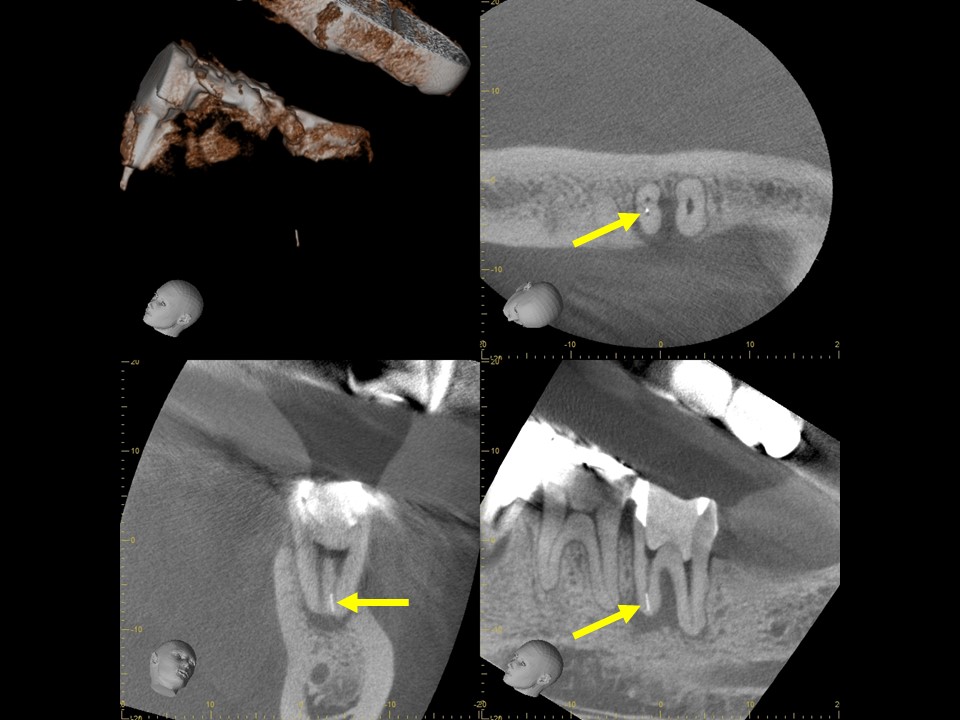

診断と治療計画の立案

当該の左下7番の奥歯はクラウンで被せてありましたが、頬側に歯茎の腫れ(フィステル、サイナストラクト)を認めました。レントゲンおよびCTによる診査を行ったところ、すでに根管治療が施してあるものの根管充填が不十分で、根尖病変を生じていました(下写真)。また、歯根の先端部分にはファイルと思われる器具の破折片を認めました(矢印)。根管内部へのバクテリアの感染による慢性化膿性根尖性歯周炎と診断し、再根管治療をおこなうことにしました。

治療前のレントゲンおよびCT画像です。当該歯はすでに根管治療が施してあり、根尖部には根尖病変によるX線透過像を認めます。

また、根尖部にはファイルと思われる器具の残存を認めます(矢印)。

ガッタパーチャを除去したところです。CT画像にて根尖部に破折しているファイルが残っているのが確認できます(矢印)。

根管充填後のレントゲンおよびCT画像です。根尖までしっかりとお薬が詰まっていることが確認できます。